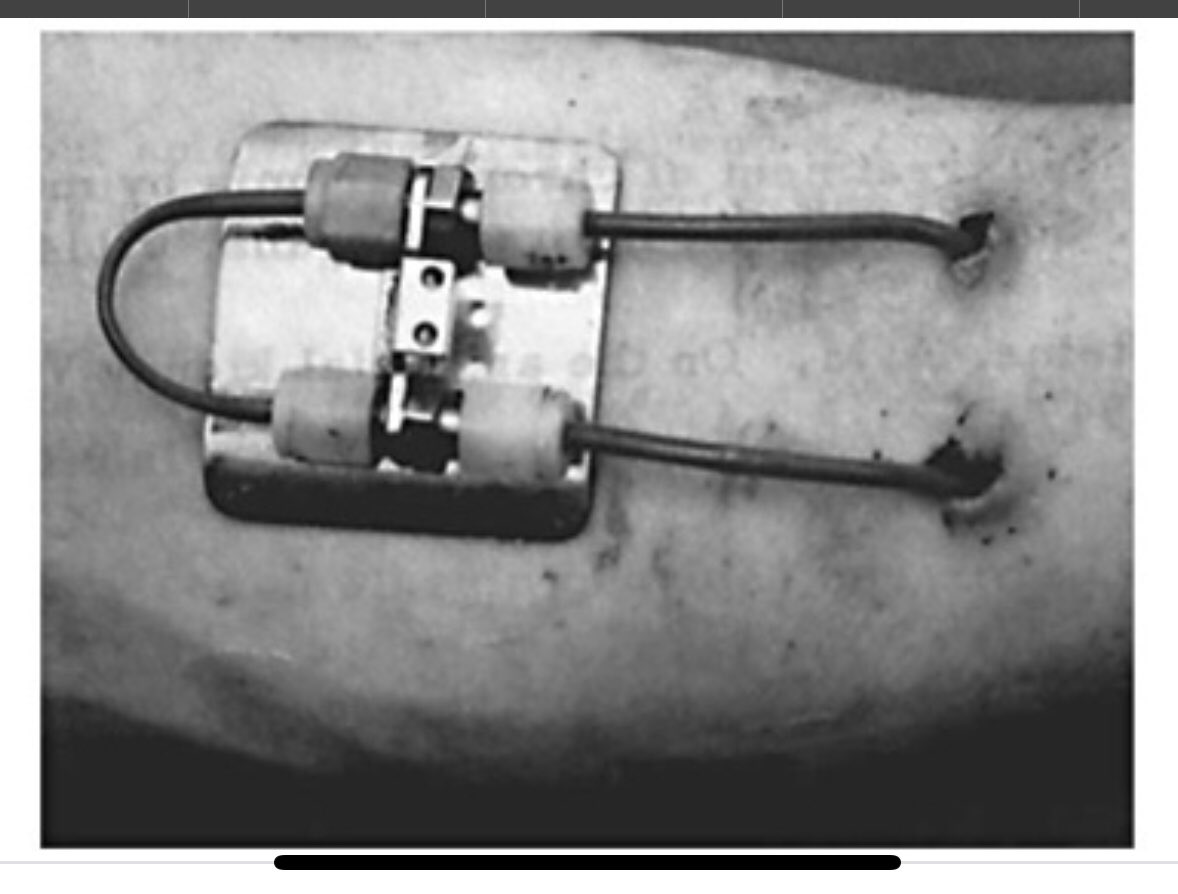

Robert Shahverdyan, MD (@robshahverdyan) 's Twitter Profile Photo

Historic day for AV-Access: this 72 y/o female patient is (to my knowledge) the very first patient in the Milky Way, who has had the oldest (#Scribner-Shunt) and the newest (#EllipsS pAVF) in same arm in >30 years! Failing NTx, Ellipsys with 720ml/min procedural flow in 12 min.